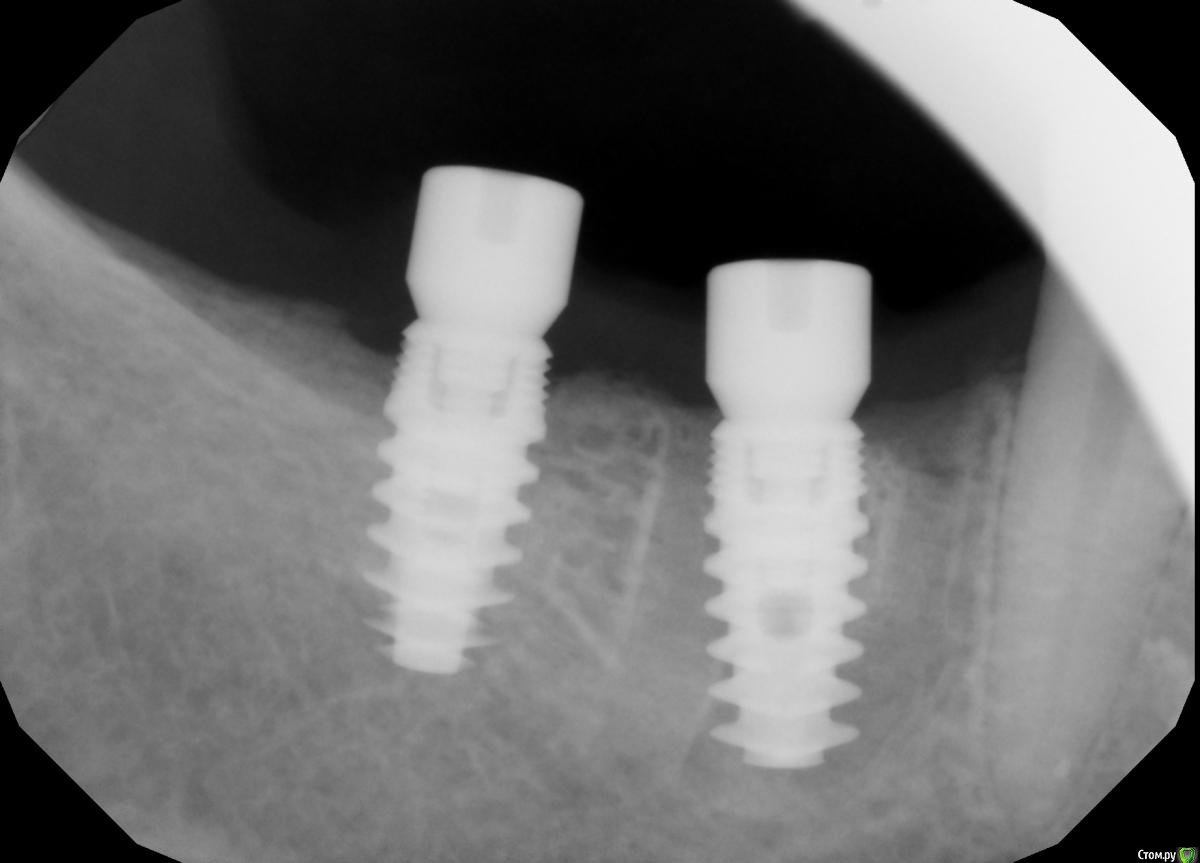

Demerchyan26 Опубликовано 3 марта, 2016 Поделиться Опубликовано 3 марта, 2016 Решил показать свой небольшой эксперемент. Ничего необычного, сложное удаление 1 час + имплантация, только без графта, лишь сгусток и торк меньше 5, не мог заглушку прикрутить. Открывал через 3,5 - 4 месяца. Система бюджетная - SGS, 7-ку немного не докрутил))) Ссылка на комментарий

red_butler Опубликовано 3 марта, 2016 Поделиться Опубликовано 3 марта, 2016 Возможно, но это не первая моя операция без графта, но первая, когда перегородки почти не осталось и торк получился минимальный, имплант слишком широкий взял.Проблема не в ширине, нужен был более длинный винт. А вот то что дистальный не досадили, это косяк, кость еще уйдет. Что с мягкими тканями? Ссылка на комментарий

Карен Аванесов Опубликовано 3 марта, 2016 Поделиться Опубликовано 3 марта, 2016 Снимков с коронками нет, и нет уверенности что эти дефекты заполнены костью. Ссылка на комментарий

diesel87 Опубликовано 3 марта, 2016 Поделиться Опубликовано 3 марта, 2016 При наличии ксено графта он будет каркасом для кортикалки, предохраняя ее от чрезмерной резорбции, пока в его пространства прорастают свежие сосуды и образуется молодая кость. На сгустке будет тоже хорошо, но с более выраженной резорбцией, но какая нам разница, имплант же там уже стоит, а вот с мягкими тканями считаю надо усиленнее работать в такой ситуации. Ссылка на комментарий